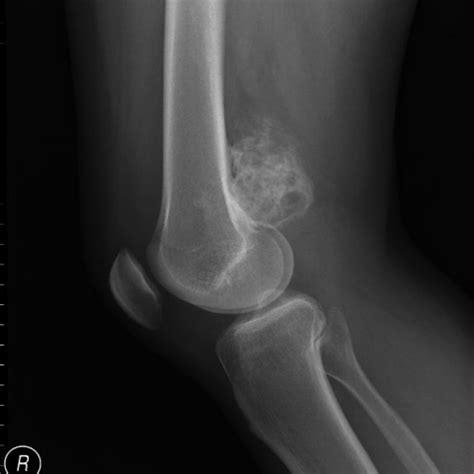

Aspectos radiográficos

La radiografía muestra una masa yuxtacortical densa, muy osificada, oval o esférica, mamelonada, de base ancha y fusiforme que parece abrazar la metáfisis. El tumor está separado de la cortical por una zona radiolucente delgada, excepto en su lugar de inserción.

La capa superficial, de formación más reciente, tiene menos densidad que la base del tumor, siendo ocasionalmente mal delimitada y poco definida, mostrando espículas o extensión lineal. Generalmente la delimitación con las partes blandas es clara. La cortical subyacente está poco afectada.

En lesiones de larga evolución se observa engrosamiento cortical por debajo del tumor y envolvimiento del hueso huésped. La destrucción cortical y la invasión medular son poco frecuentes y solo en casos avanzados. También es rara la reacción perióstica.

Hallazgo radiológico característico